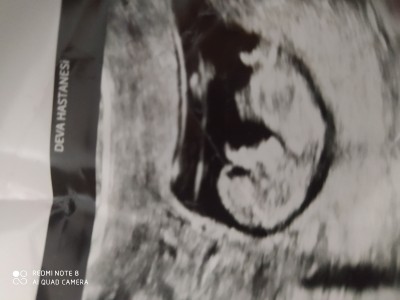

Bugün doktora gittim kızlar,11+2 haftalık şu pipisi olabilir erkeğe benziyor dedi tahmin edermisiniz

Gebelik haftası 11+2